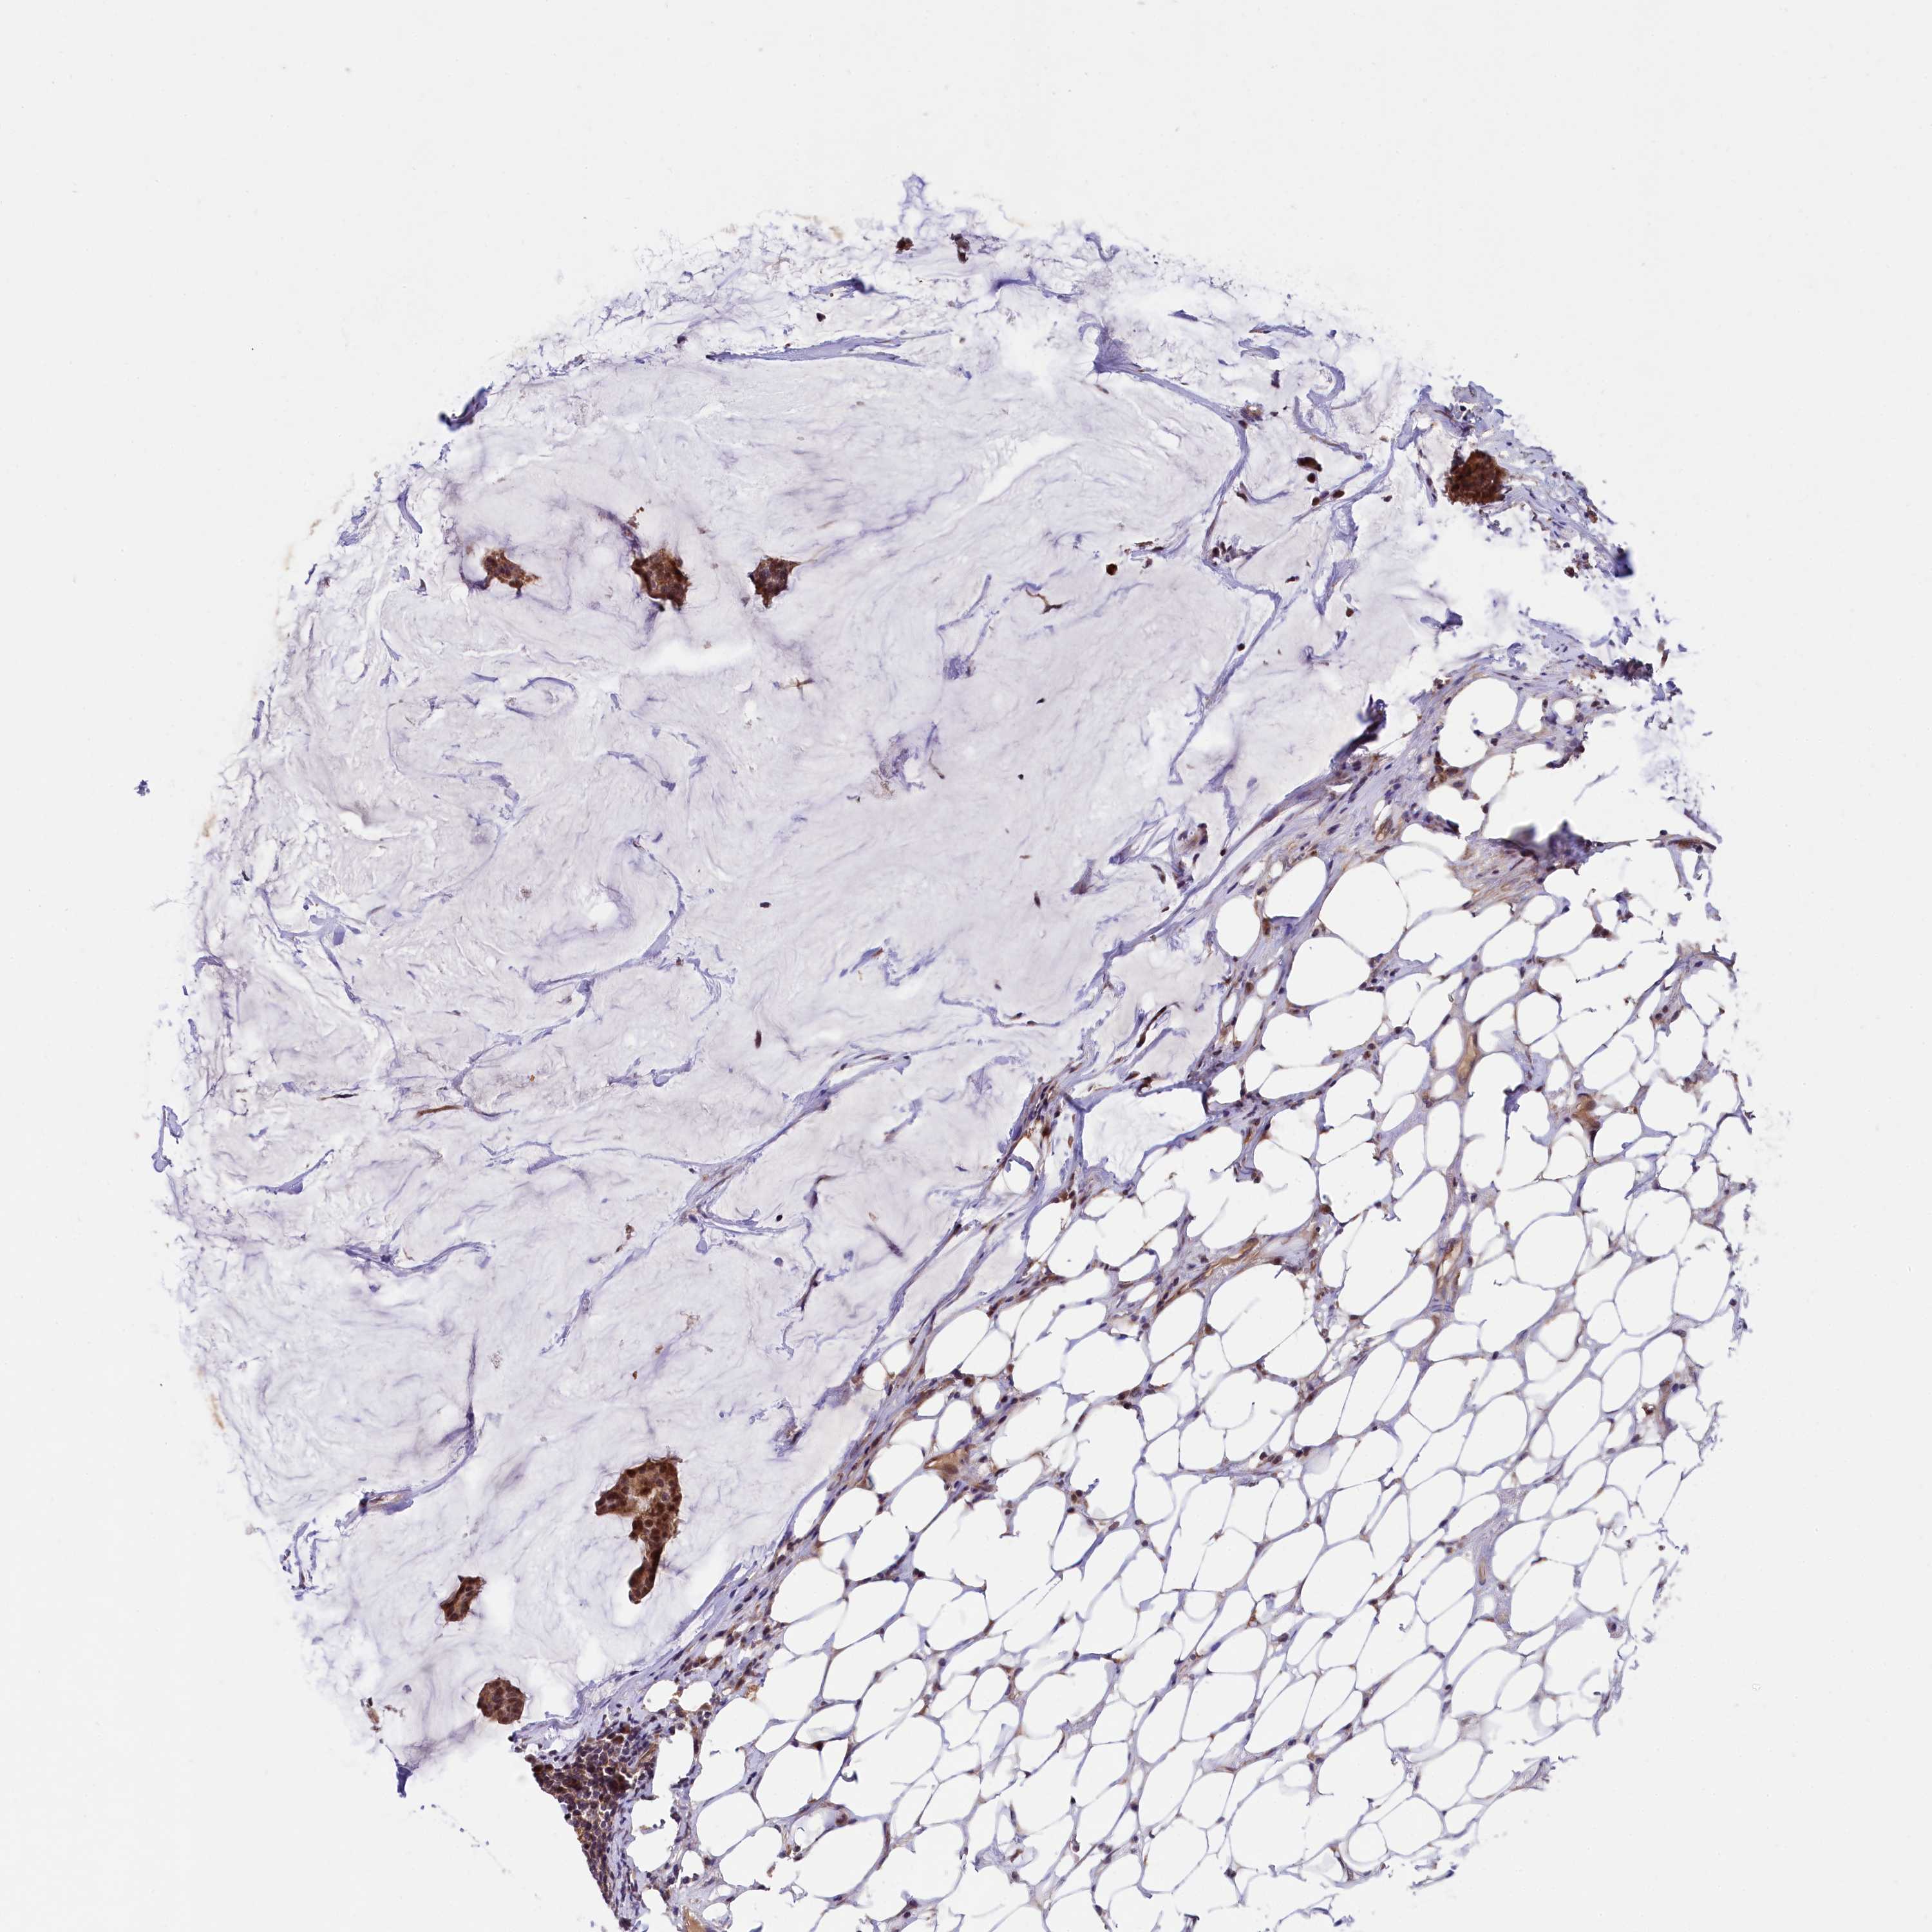

CANCER BREAST CANCER Show tissue menu

BRCA TCGA BRCA VALIDATION PROTEIN EXPRESSION